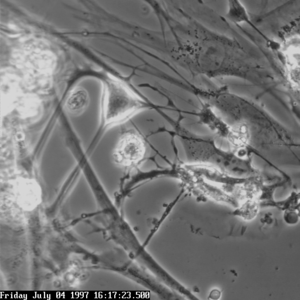

The picture to the right shows an isolated interstitial cell of Cajal from the myenteric plexus of the mouse small intestine grown in a primary cell culture. This cell type can be characterized morphologically as having a small cell body often triangular or stellate-shaped with several long processes branching out into secondary and tertiary extensions - these processes often contact smooth muscle cells. They have contractile behaviour in both the cell body and the extended processes.